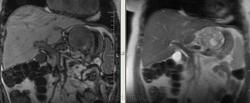

Интересные брюшные полости пошли в последнее время. Женщина, 1941 г.р. Оформлялась на операцию (по глазам), прошла УЗИ, после чего направили к нам. Жалобы только на глаза и суставы, на брюшную полость никаких. 2 года назад делала ФГС - все в порядке было. Коллеги, подскажите, пожалуйста, откуда растет эта штука? Из брюшины? Или из желудка? Или еще откуда-то?

Как-то очень близко к желудку прилежит, даже местами четко граница не прослеживается.

Согласен с Алексеем Станиславовичем. Опухоль связана со стенкой желуда, что видно на сканах 76, 77, 110, 111, стенка желудка истончена, накапливает контраст. На лейомиому в чистом виде опухоль не очень похожа, как я её себе представляю, зоны деструкции, кровоизлияния, может быть малигнизированная если. Но выглядит довольно доброкачественно в плане операбильности, имеет капсулу (не в месте контакта с желудком). Мне недавно попадалась опухоль точно такой же локализации, но имела совершенно другую структуру, прилежала к брюшине без явных признаков прорастания её. Пациентка врач, я думаю узнаю гистологию у неё, но та выглядела злокачественной.